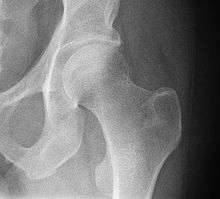

- Hip joint. Lateral view.